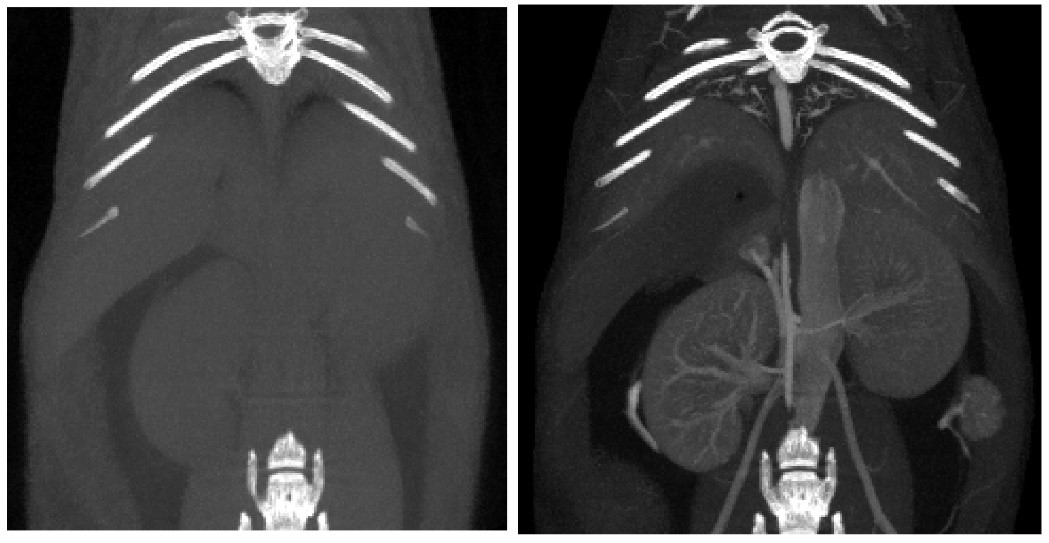

(1)活体(in vivo):研究对象为活体小鼠和大鼠,可以实现生理代谢功能的纵向研究。和临床CT相似,活体小动物CT也能够进行呼吸/心跳门控和显影剂增强扫描;

(2)离体(in vitro):研究对象是离体标本(如骨骼、牙齿)或各种材质的样品。也可以使用凝固型造影剂灌注活体动物,对心血管系统、泌尿系统或消化系统进行精细成像。